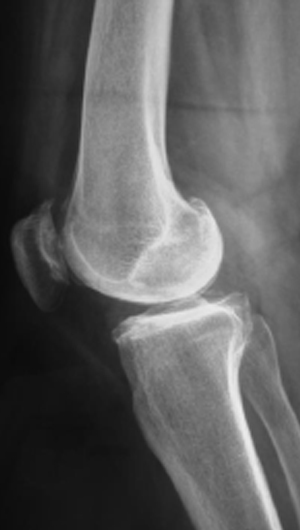

En la radiografía de la izquierda se observa la asimetría entre los espacios de la articulación de la rodilla, el lado lateral se observa separado y hacia el lado contrario se presenta un desgaste o pinzamiento entre los dos huesos que se traduce como una pérdida del cartílago o cojinete articular.

La radiografía de la derecha es la toma con la rodilla de lado que muestra desgaste entre la rotula y el fémur.